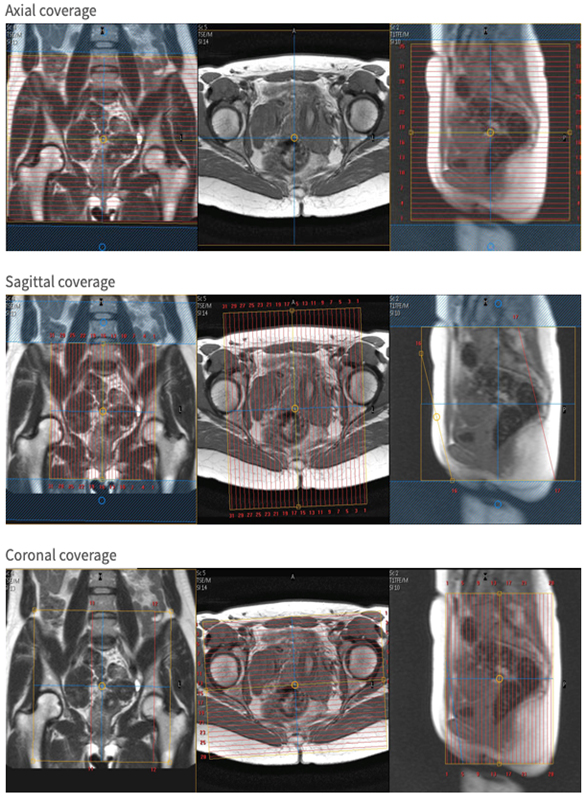

| AX | T2 | SSTSE | 5mm | 1mm | No | 300-380 mm Fit to Patient | Consider anterior sat band if lots of abdominal wall motion.Cover fovea to fovea, encompassing the entire uterus. |

| SAG | T2 | SSTSE | 5mm | 1mm | No | 300-380 mm Fit to Patient | Frequency A-PUse anterior sat band Cover fovea to fovea, encompassing the entire uterus. |

| COR | T2 | SSTSE | 5mm | 1mm | No | 300-380 mm Fit to Patient | Cover the entire uterus. |

| AX | T2 | bFFE | 3.5mm | 1.2mm | No | 300-390 mm fit to patient | Consider anterior sat band if lots of abdominal wall motion.Cover fovea to fovea, encompassing the entire uterus. |

| SAG | T2 | bFFE | 3.5mm | 1.2mm | No | 300-390 mm fit to patient | Frequency A-PUse anterior sat band.Cover fovea to fovea, encompassing the entire uterus. |

| COR | T2 | bFFE | 3.5mm | 1.2mm | No | 300-390 mm fit to patient | Cover the entire uterus. |